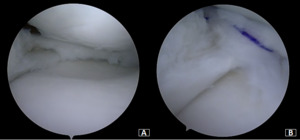

Under general anesthesia, a left knee arthroscopy using standard anterolateral and anteromedial portals. An incomplete type medial discoid meniscus with an atypical hypertrophic posterior root and an enlargement of the body and the posterior horn of the meniscus was found (Figure 3A). In addition, instability of the posterior horn, with a lack of rear tibial attachments, was observed (Figure 3B). Saucerization of the central discoid element was performed until an average meniscal width and semilunar shape was reached (Figure 4A). Two outside-in sutures with absorbable stitches were thus applied to repair the horizontal tear and stabilize the meniscus’s peripheral rim to the knee capsule (Figure 4B). A probe was used to assess the repair’s tightness and stability. Because the right knee was paucisymptomatic, no treatment was performed.